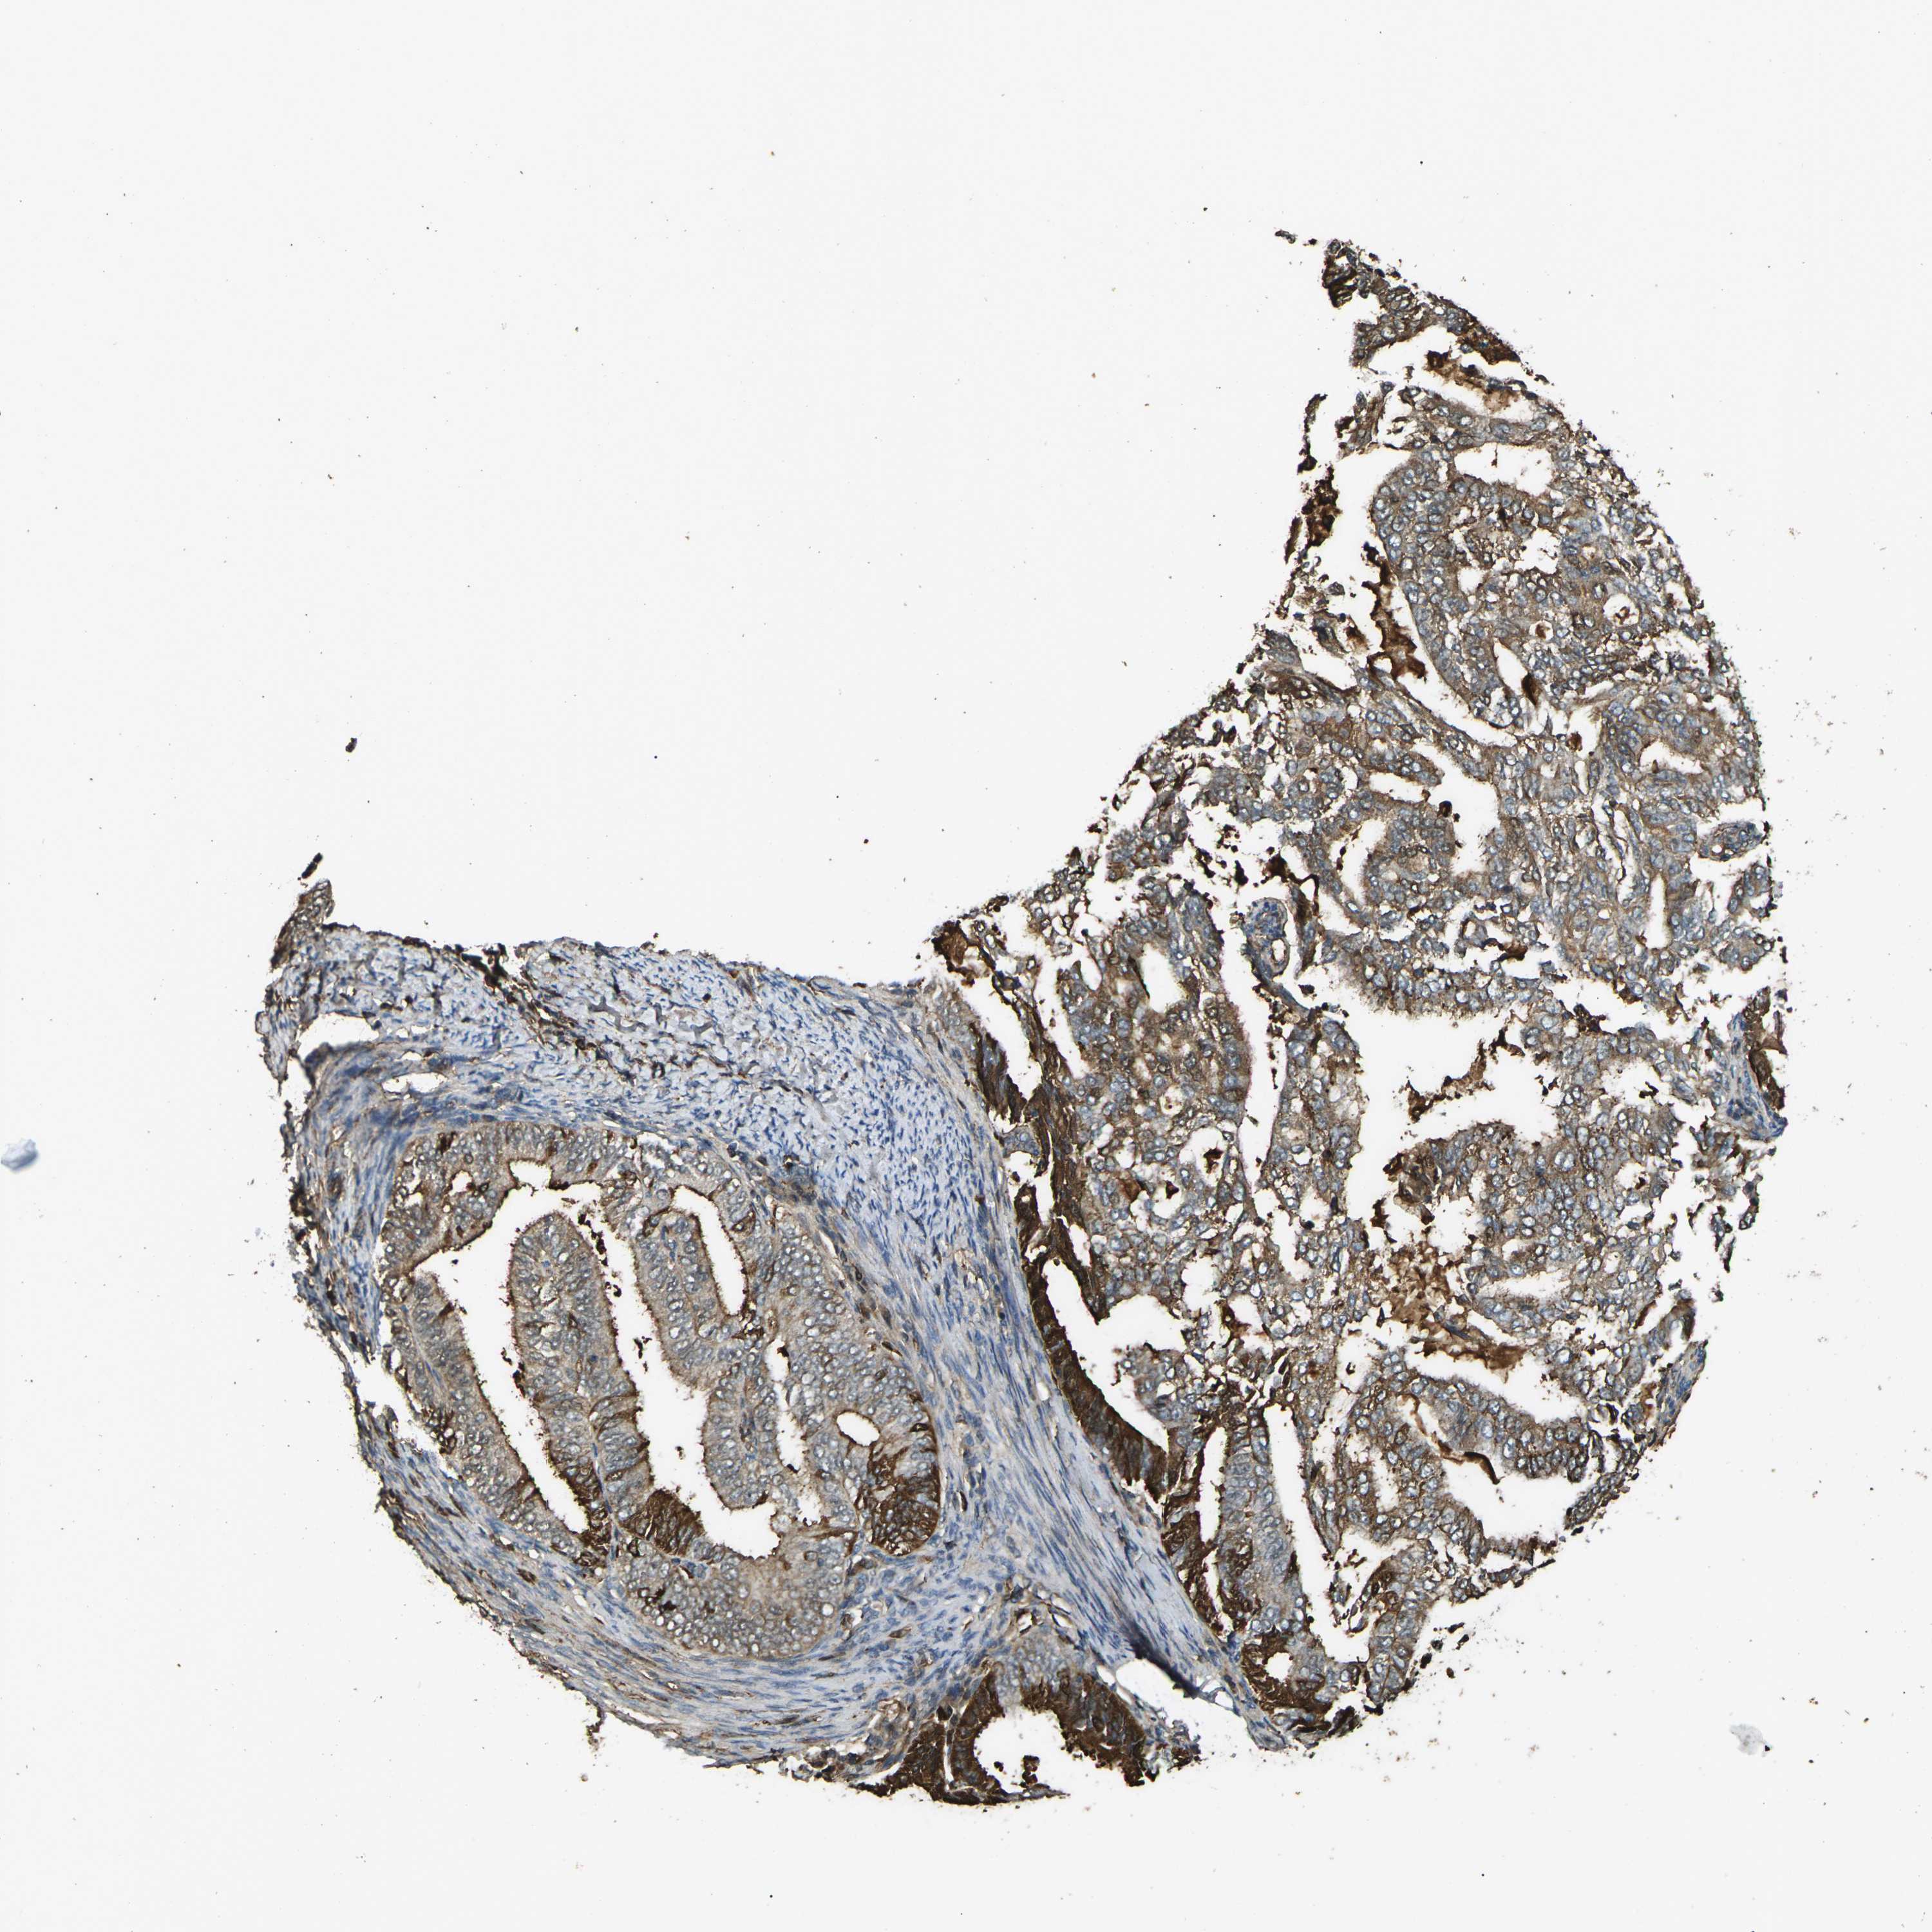

ENDOMETRIAL CANCER - Protein expressioni

A mouse-over function shows sample information and annotation data. Click on an image to view it in a full screen mode. Samples can be filtered based on level of antibody staining by selecting one or several of the following categories: high, medium, low and not detected. The assay and annotation is described here.

Note that samples used for immunohistochemistry by the Human Protein Atlas do not correspond to samples in the TCGA dataset.

Antibody stainingi

Antibody staining in the annotated cell types in the current human tissue is reported as not detected, low, medium, or high, based on conventional immunohistochemistry profiling in selected tissues. This score is based on the combination of the staining intensity and fraction of stained cells.

Each image is clickable and will lead to virtual microscopy that enables deeper exploration of all samples and also displays staining intensity scores, fraction scores and subcellular localization as well as patient and tissue information for each sample.

Antibody HPA026863

Antibody CAB011705

Staining

High

Medium

Low

Not detected

Intensity

Strong

Moderate

Weak

Negative

Quantity

>75%

75%-25%

<25%

None

Location

Nuclear

Cytoplasmic/membranous

Cytoplasmic/membranous,nuclear

Adenocarcinoma, NOS

Adenocarcinoma, metastatic, NOS